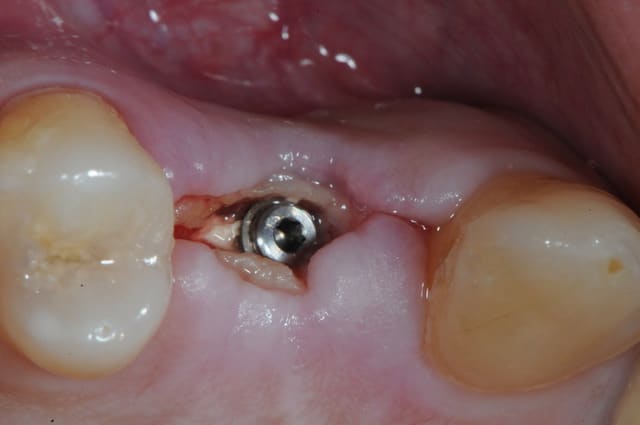

dis moi la tu le trouves comment mon compromis avec l'espace biologique

eii

d'après toi faites il y a combien de temps?

Superbe ratrapage suite à une operculisation d'une vis de couverture. Félicitations. Je te savais costaud béotien mais là tu m'impressionnes vraiment.

- pas de vis de couverture , pas d'operculisation!!

Même pas de lambeau pédiculé palatin!